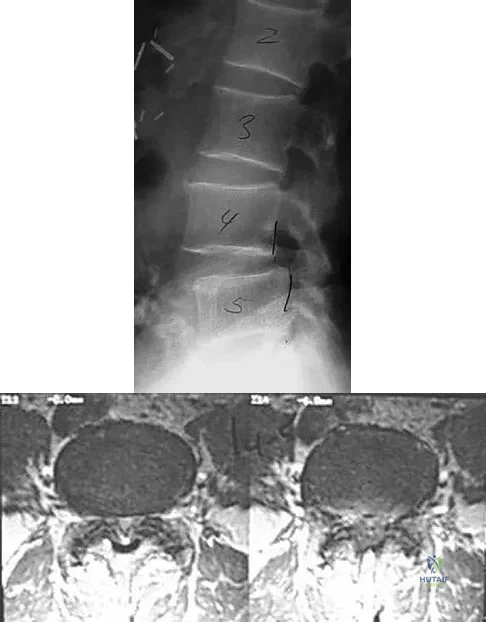

Question 77High Yield

An otherwise healthy 70-year-old man has back and bilateral leg pain in an L5 distribution that is aggravated by standing more than 10 minutes or walking more than 100 feet. He has to sit to get relief. Neurologic and pulse examinations are normal. A radiograph and MRI scan are shown in Figures 4a and 4b. Treatment should consist of

Explanation